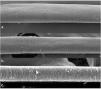

A 72-year-old patient who had received ibrutinib for six months to treat mantle lymphoma unresponsive to conventional therapy was assessed. The patient reported a slight alteration in his hair, with a change in its curling (Fig. 1). Some hair shafts were cut and examined in natura with scanning electron microscopy. At medium magnification, discreet longitudinal channels were observed in the hair shafts (Fig. 2A and B), which are not seen in normal hair (Fig. 2C). At high magnification, these channels were very evident (Figs. 3 and 4).

The authors did not find any reports in the literature of an examination of hairs shafts with scanning electron microscopy showing alterations caused by ibrutinib. There are some reports with EGF inhibitors, in which channels were also described in the hair shafts,9 in this case with greater clinical consequences, making the hair frizzy and the eyelashes elongated (trichomegaly) and without curvature. The channels seen in these drug-induced cases are similar to those seen in families with uncombable hair,10 and in a syndromic type of pili canaliculi associated with a central nervous system degeneration called giant axonal neuropathy.11

The findings of this patient demonstrate, on ultrastructural examination, a similarity between the alterations of EGF and BTK inhibitors.